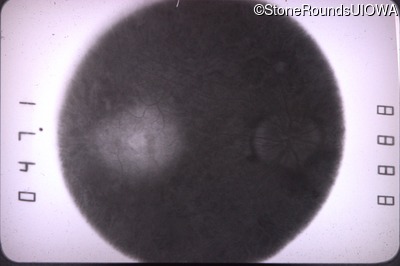

Infrared Fundus Photograph - Right - 20/60 -1

Exemplar